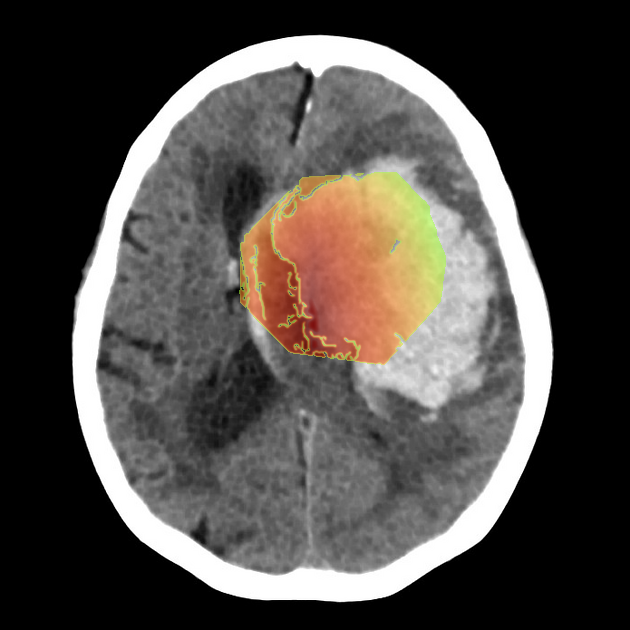

- Large hyperdense intra-axial hematoma centered in the basal ganglia region on the image-right (patient-left).

- Dimensions appear to exceed 4 cm in maximal diameter, consistent with a high-volume hemorrhage.

- Marked surrounding low-density area representing vasogenic edema.

- Significant mass effect with compression of the ipsilateral lateral ventricle and effacement of cortical sulci.

- Midline shift of approximately 8–10 mm towards the image-left (patient-right).

- Deformation and partial effacement of the third ventricle, raising concern for obstructive hydrocephalus.

- No extra-axial hemorrhage evident in this slice.

The most likely diagnosis is a large acute intracerebral hemorrhage involving the image-right (patient-left) basal ganglia. This is supported by the hyperdense appearance of acute blood, classic deep location, and associated edema with mass effect. Hypertensive intracerebral hemorrhage is the most common etiology, especially in the basal ganglia region. The degree of shift and ventricular compression indicates a life-threatening presentation.